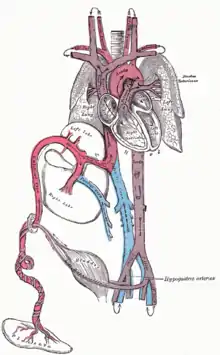

Circulatory system

Before birth

The heart and blood vessels of the circulatory system form relatively early during embryonic development, but continue to grow and develop in complexity in the growing fetus. A functional circulatory system is a biological necessity since mammalian tissues can not grow more than a few cell layers thick without an active blood supply. The prenatal circulation of blood is different from postnatal circulation, mainly because the lungs are not in use. The fetus obtains oxygen and nutrients from the mother through the placenta and the umbilical cord.[26]

Blood from the placenta is carried to the fetus by the umbilical vein. About half of this enters the fetal ductus venosus and is carried to the inferior vena cava, while the other half enters the liver proper from the inferior border of the liver. The branch of the umbilical vein that supplies the right lobe of the liver first joins with the portal vein. The blood then moves to the right atrium of the heart. In the fetus, there is an opening between the right and left atrium (the foramen ovale), and most of the blood flows from the right into the left atrium, thus bypassing pulmonary circulation. The majority of blood flow is into the left ventricle from where it is pumped through the aorta into the body. Some of the blood moves from the aorta through the internal iliac arteries to the umbilical arteries and re-enters the placenta, where carbon dioxide and other waste products from the fetus are taken up and enter the mother's circulation.[26]

Some of the blood from the right atrium does not enter the left atrium, but enters the right ventricle and is pumped into the pulmonary artery. In the fetus, there is a special connection between the pulmonary artery and the aorta, called the ductus arteriosus, which directs most of this blood away from the lungs (which are not being used for respiration at this point as the fetus is suspended in amniotic fluid).[26]

Postnatal development

With the first breath after birth, the system changes suddenly. Pulmonary resistance is reduced dramatically, prompting more blood to move into the pulmonary arteries from the right atrium and ventricle of the heart and less to flow through the foramen ovale into the left atrium. The blood from the lungs travels through the pulmonary veins to the left atrium, producing an increase in pressure that pushes the septum primum against the septum secundum, closing the foramen ovale and completing the separation of the newborn's circulatory system into the standard left and right sides. Thereafter, the foramen ovale is known as the fossa ovalis.

The ductus arteriosus normally closes within one or two days of birth, leaving the ligamentum arteriosum, while the umbilical vein and ductus venosus usually closes within two to five days after birth, leaving, respectively, the liver's ligamentum teres and ligamentum venosus.